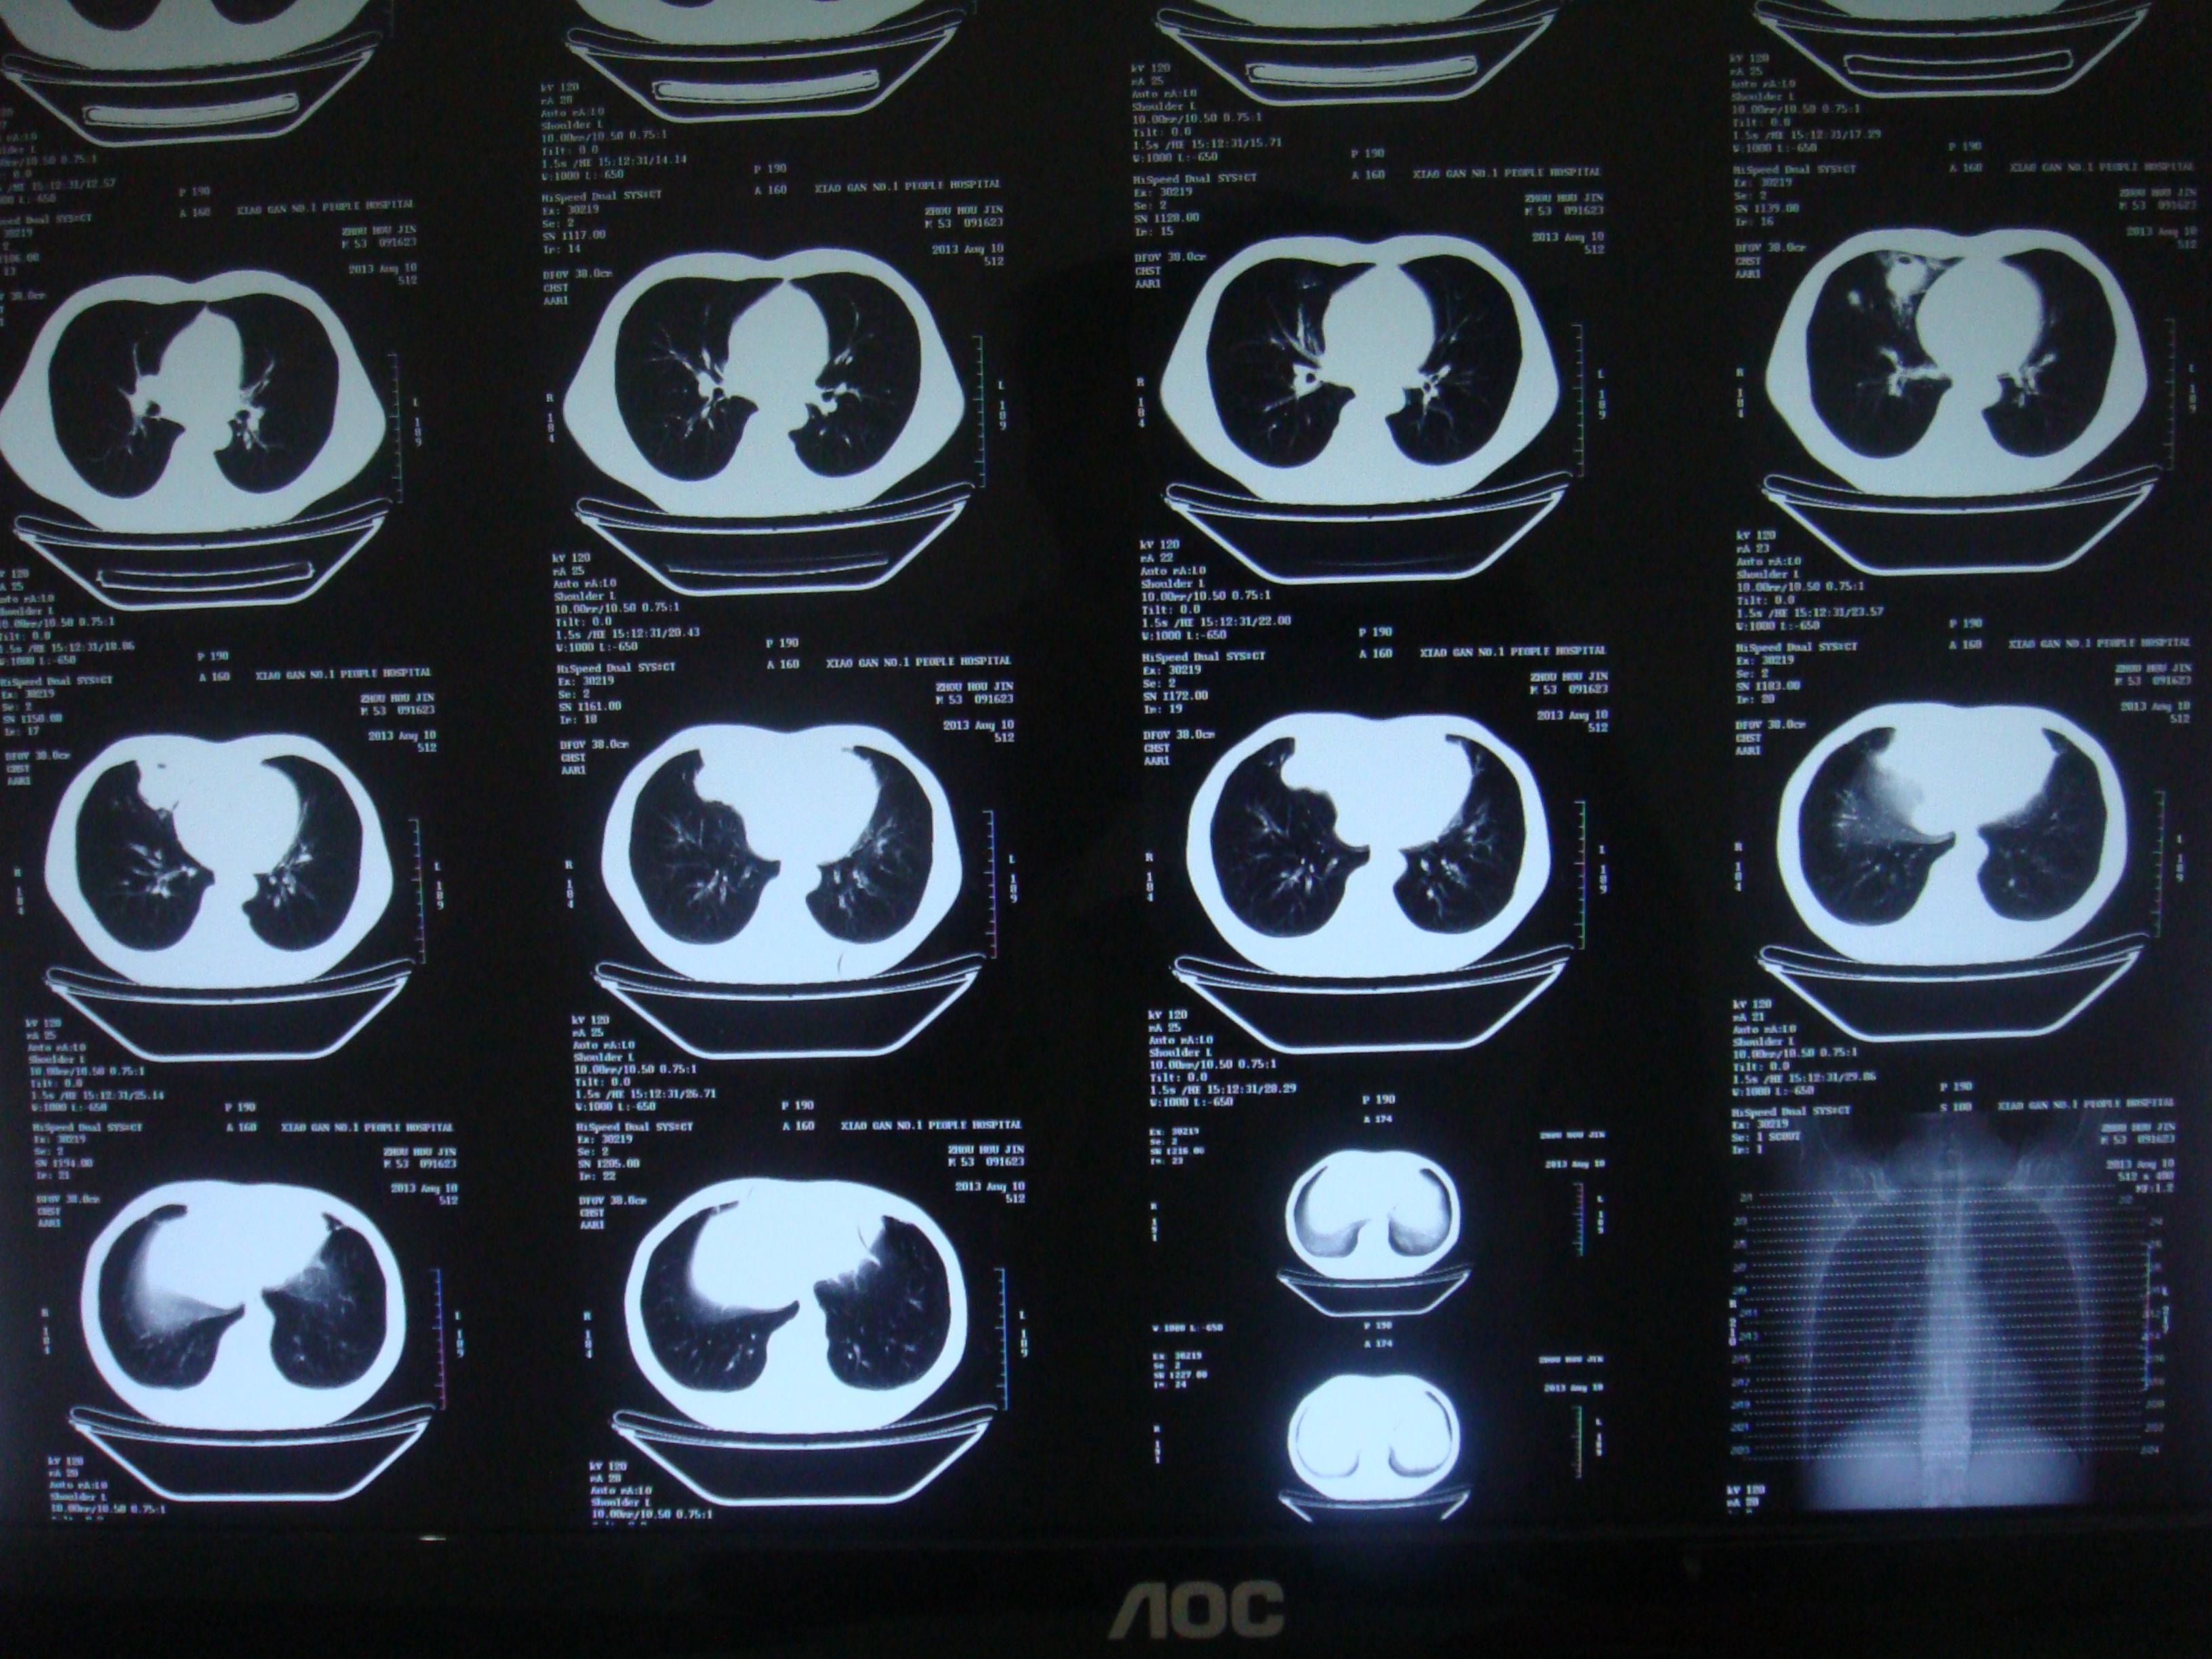

吸入性化脓性肺炎紧急求助

肺炎ct表现

1例"特殊"的吸入性肺炎

患者刘爷爷因误吸药丸出现呛咳,气促紧急入院,胸部ct显示,左下叶支